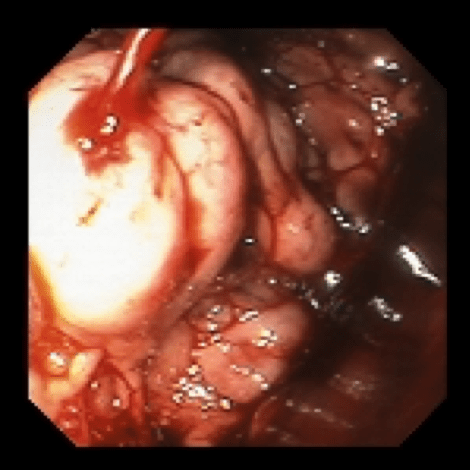

Therapeutic procedures that can be done during endoscopy are:

- Endotherapy of ulcers